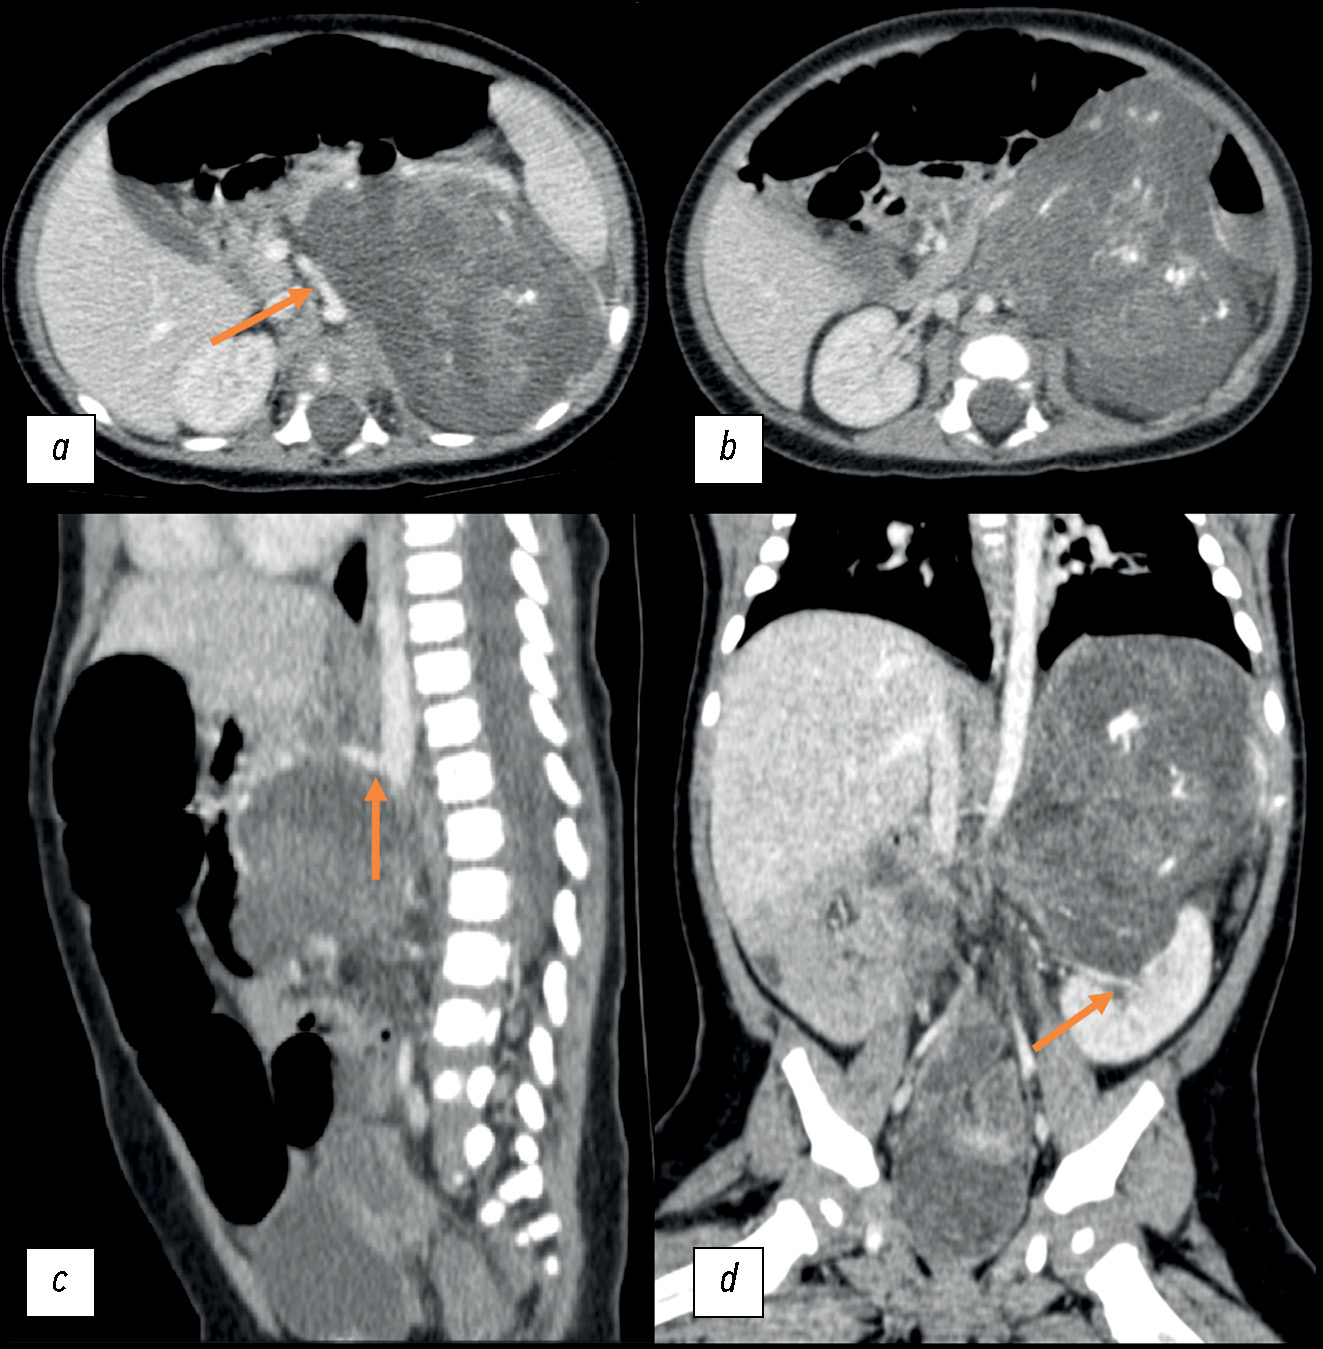

September 23, 2020: A contrast-enhanced abdominal multislice computed tomography (MSCT) revealed a retroperitoneal space-occupying mass on the left, measuring 81 × 71 × 87 mm (volume: 260 cm3), with a heterogeneous structure incorporating areas of calcification and inclusion cysts; the contrast uptake was weak. The neoplasm extended to the renal sinus area, without discernible signs of extension into the renal parenchyma. The adrenal gland extended across the lateral contour. The renal vessels on the left side followed the tumor contour; the superior mesenteric artery was displaced to the right, while the celiac artery was displaced upward (Fig. 1).

Fig. 1. Initial abdominal computed tomography using intravenous contrast dated September 23, 2020, a pattern of a space-occupying retroperitoneal mass on the left: (a) axial plane; the arrow indicates the displacement of the superior mesenteric artery to the right; (b) axial plane; (c) sagittal plane; the arrow indicates the upward displacement of the celiac artery; (d) coronal plane; the arrow indicates the tumor extension into the renal sinus.

Considering an increase in the tumor size during the initial chemotherapy course, tumor characteristics with signs of fat deposits and tumor infiltration of the renal sinus area, as well as the absence of cytogenetic test findings, surgery was recommended. This procedure included repeated laparotomy and retroperitoneal tumor resection to conduct routine histopathological examination and cytogenetic testing.

Moreover, the diagnosis of adrenal teratoma was inferred from the clear and smooth contours of the tumor, which displaced vessels without surrounding them; in contrast, neuroblastoma exhibits indistinct, irregular contours and affects vessels by infiltrating them. The presence of a cystic and solid component and calcification is typical for both tumors. The absence of radiopharmaceutical uptake during scintigraphy, low NSE levels, and high AFP levels are also suggestive of teratoma. The histopathological examination’s errors may be attributed to a biopsy performed at a less informative site and a limited sample size.